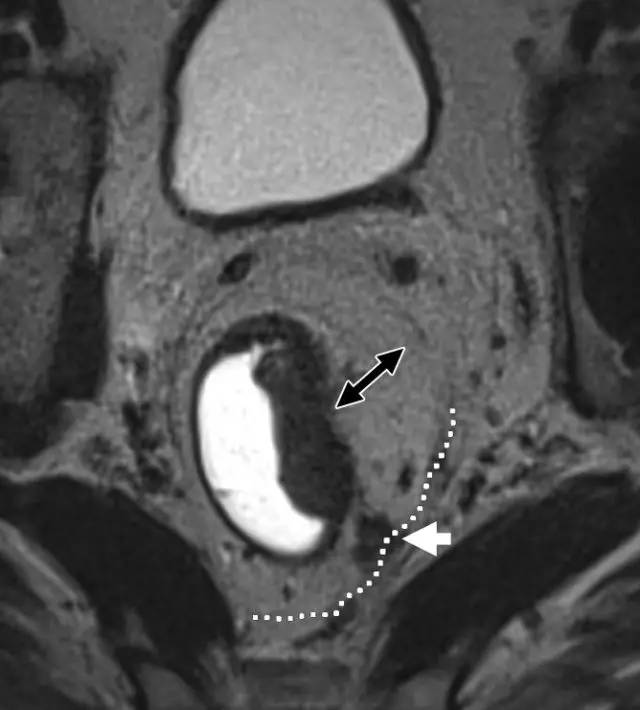

壁外血管侵犯 EMVI

多达一半的结直肠癌病例发生 EMVI,是局部复发、远处转移和较差 OS 的独立危险因素。EMVI 是在直肠固有肌层以外直肠系膜的血管内存在恶性细胞。MR 成像描绘的 EMVI 的严重程度与 DFS 相关。

EMVI 的诊断线索:

1. 根据定义,EMVI 必须与至少 T3 类肿瘤有关。T1 或 T2 不具有侵入外部血管的潜力。

2. 只要肿瘤靠近血管,就应该考虑 EMVI 的可能性。

3. EMVI 的迹象:(1)在血管结构内存在肿瘤信号强度;(2)血管扩张;(3)肿瘤扩张通过和超出血管壁,破坏血管边界。

4. 最后,如果存在 EMVI,必须考虑所涉及静脉是否威胁到直肠系膜筋膜(即它们是否在筋膜的 1 mm 以内)。

为了更为准确的判断 EMVI,根据肿瘤外形,肿瘤周围是否存在血管,受累血管管径、轮廓及信号的变化,MRI 评估直肠癌 EMVI 的 5 级评分系统,并将评分为 0~2 定义为阴性,3 和 4 的定义为 EMVI 阳性。